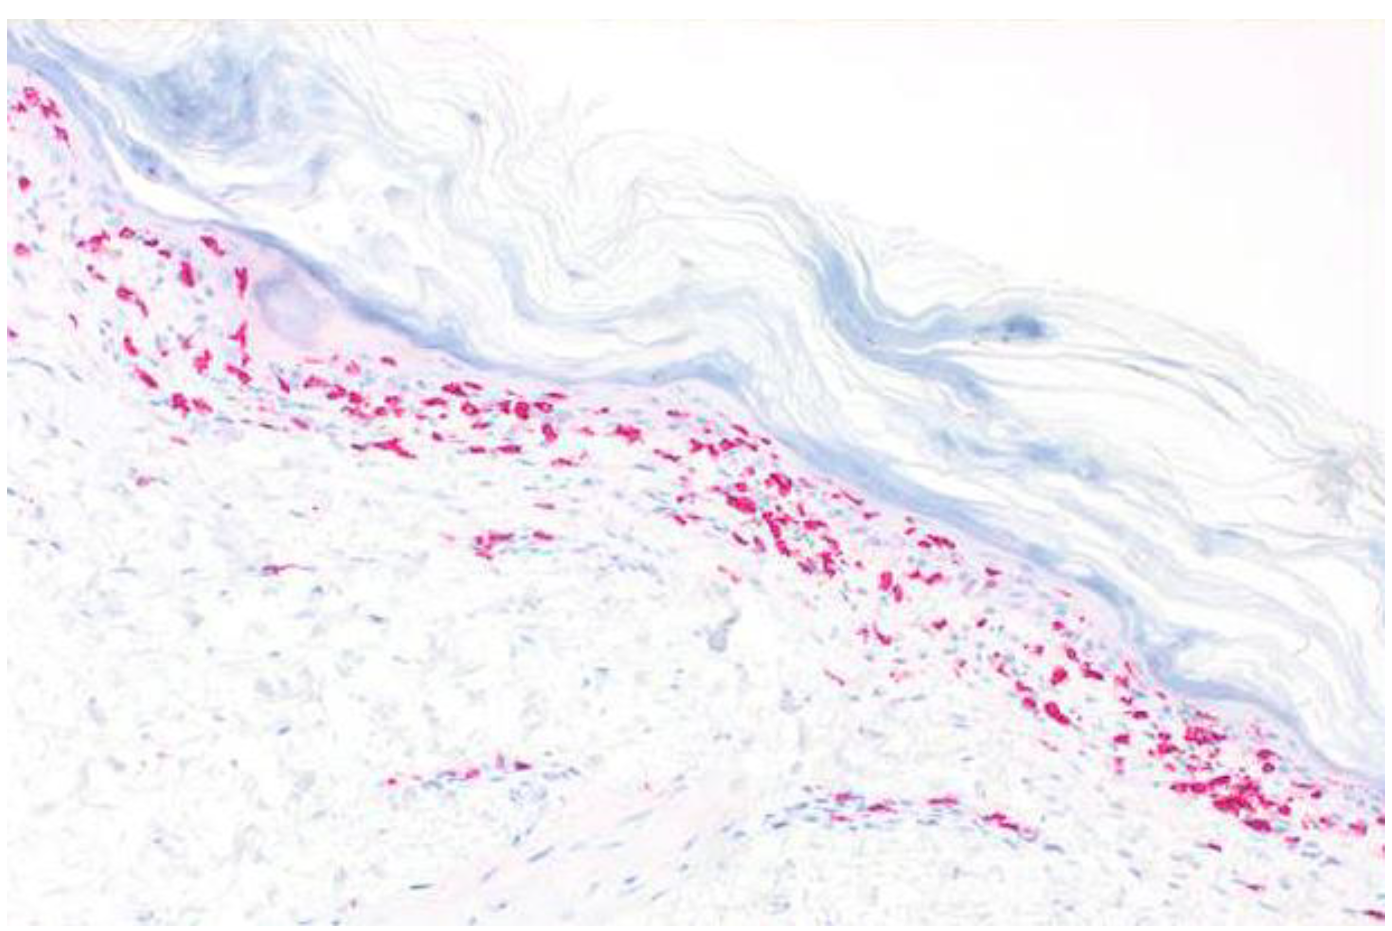

A skin biopsy revealed a similar histopathological pattern as that observed in July 2020. Immunohistochemistry for cytotoxic lymphocytes revealed an abundance of CD8+ cells along the dermoepidermal junction zone, with marked epidermotropism (Figure 6). T-cell receptor rearrangement studies did not reveal evidence for T-cell lymphomas, such as primary cutaneous CD8+ aggressive epidermotropic cytotoxic T-cell lymphoma. In order to confirm PAMS, we carried out several laboratory tests. However, direct and indirect immunofluorescence studies did not reveal IgG or IgA autoantibodies. The ELISA for circulating BP-230, desmoglein 1 and 3, and envoplakin autoantibodies was negative.

Figure 6.

Immunohistology showing strong band-like immunoreactivity for CD8+ lymphocytes along the dermoepidermal junction zone, with strong epidermotropism.

The histologic findings in PAMS include epidermal acantholysis and clefting, the presence of necrotic keratinocytes, vacuolization of the basal layer, and lymphocyte exocytosis. Dyskeratosis, with suprabasal acantholysis, is a characteristic feature of PAMS in most cases. However, histopathologic features may vary with the particular morphology of the lesions, ranging from non-inflammatory bullous lesions to dense non-blistering lichenoid inflammatory infiltrates. Interface dermatitis, secondary to a T-cell-mediated autoimmune reaction, and subsequent infiltration into the epidermis suggest a strong cell-mediated cytotoxicity component in PAMS. Indeed, by immunohistochemistry, we observed a dense CD8+ lymphocytic infiltrate, associated with strong epidermotropism. Similarly, Kokubu et al. also observed a follicular lymphoma patient with TEN-like PAMS, showing an abundance of CD8+ cells infiltrating into the epidermis [17]. Importantly, we observed, for the first time, a chronic excess of peripheral cytotoxic lymphocytes, accompanied by significant inversion of the CD4/CD8 ratio, in a patient with PAMS. The chronically increased levels of CD8+ cells in the peripheral blood seem to indicate systemic cell-mediated autoimmunity, which was also reflected by the strong epidermotropic infiltrates of cytotoxic lymphocytes in the skin lesions. We can only speculate whether such an excess of CD8+ cells was also present in other organs, such as the esophagus and lungs. Importantly, the pathogenetic significance of cytotoxic cells in patients with PAMS or bronchiolitis obliterans has been previously emphasized by many authors [17,18,19,20,21,22,23,24].